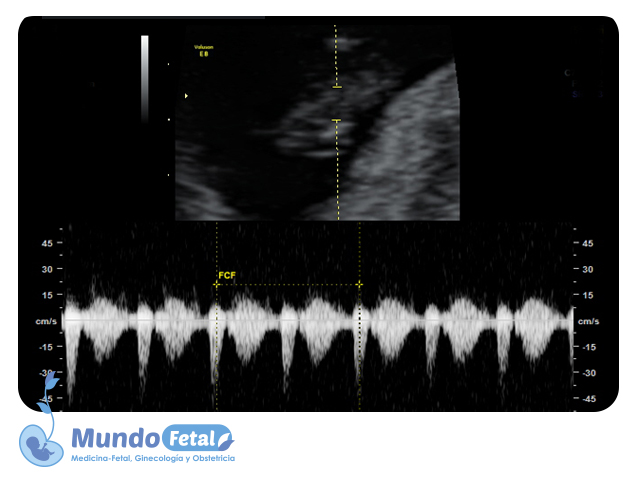

Ultrasonido Temprano 1er Trimestre (Menor 11 Semanas)

Estudio que nos permite la confirmación del embarazo, numero de bebes, valoración de líquido amniótico, placenta, vitalidad por medio de la frecuencia cardiaca, crecimiento armónico y edad gestacional estimada, descartando alguna complicación propia de esta edad.